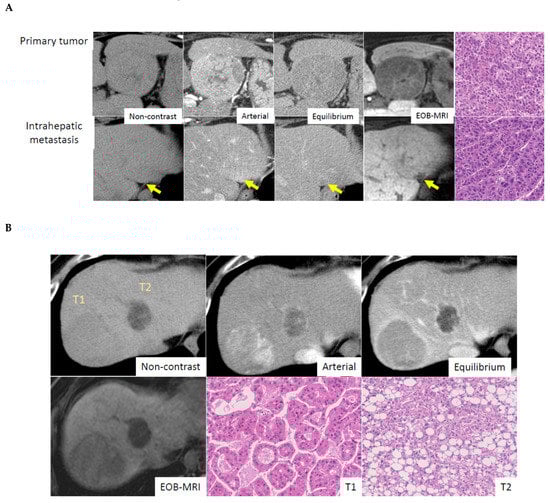

Multiple tumors are a frequent phenomenon in HCC, with an incidence around 40–50%. Importantly, multiple HCCs are characterized by two patterns, intrahepatic metastasis (IH) and multicentric occurrence [7]. IH is a multiple tumor composed of a primary tumor associating with multiple smaller tumors, which are metastatic tumors from the primary tumor. The main tumor is usually a moderate and/or poorly differentiated HCC, and the smaller metastatic tumors show similar features to that of the primary tumor. In contrast, multicentric occurrence is considered a de novo cancer, meaning that all the tumors are independent, and their differentiation and morphology are different. The occurrence of MC is significantly higher in HCV-related cases compared with HBV-related cases [16]. Molecular data confirms this, and surprisingly, 30–76% of multiple tumors are found to be MC [17,18]. The distinction between IH and MC can be made by pathological examination. MC cases show HCC containing the portal tracts, considered early HCC, or the presence of early HCC-like areas in the periphery of the HCC, or distinct histology [16]. Figure 3 illustrates the differences between IH and MC.

Figure 3.

Radiological-, and pathological features in multiple HCC (A) Intrahepatic metastasis. Primary tumor shows early enhancement and late washout pattern on CT and shows low intensity on EOB- MRI. Intrahepatic metastatic small lesion shows almost identical enhancement pattern to primary tumor. Histological features are similar between primary and intrahepatic metastatic lesion, which are moderately differentiated HCC with trabecular pattern. Courtesy of Dr. Akihisa UENO (Keio University, Tokyo, Japan). (B) Multicentric occurrence. Tumor No.1 (T1) shows early enhancement and late washout pattern on CT and shows uptake of gadolinium ethoxybenzyl diethylenetriaminepentaacetic acid (Gd-EOB-DTPA) on gadoxetic acid-enhanced magnetic resonance imaging (EOB-MRI). Histologically, tumor shows a moderately differentiated HCC with pseudoglandular pattern. Tumor No.2 (T2) shows low attenuation on non-contrast CT, indicating fatty component, and weak early enhancement and late washout. EOB-MRI reveals low intensity, which means no uptake of Gd-EOB-DTPA. Tumor pathology is steatohepatitic HCC. Courtesy of Dr. Akihisa UENO (Keio University, Tokyo, Japan).